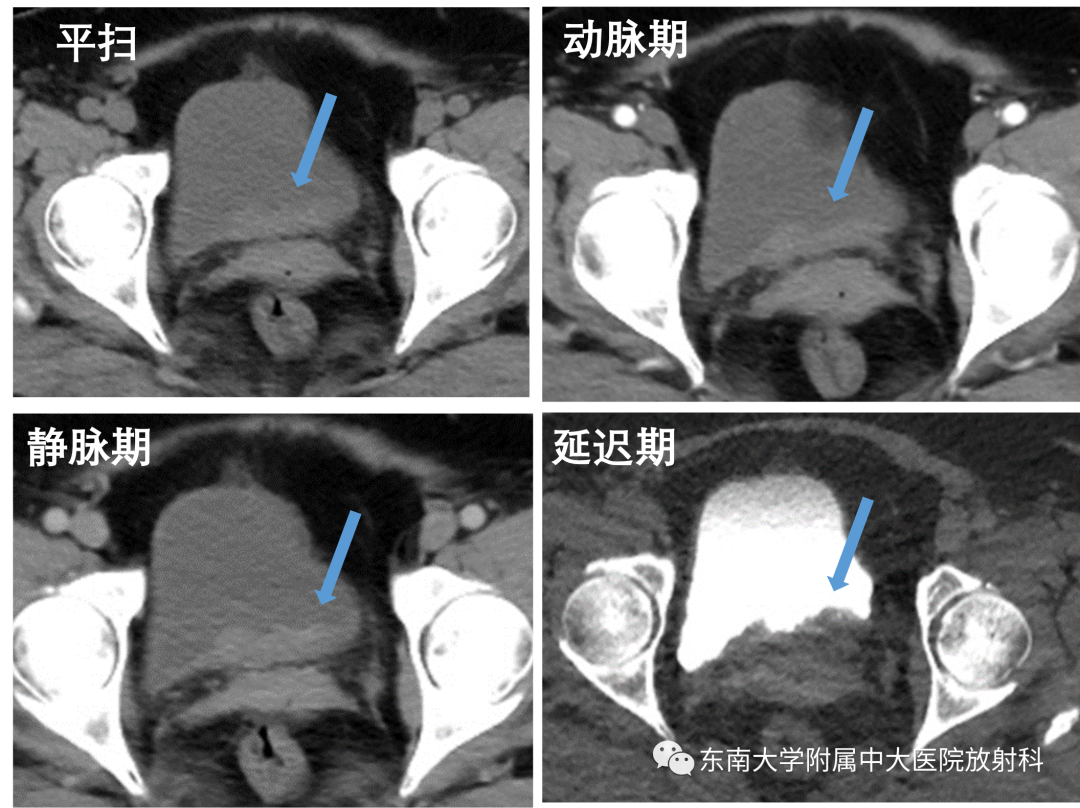

病例一

•女,65岁

•主诉:无痛性肉眼血尿1年

•现病史:患者于1年前无明显诱因下出现肉眼血尿,无尿急尿痛,无腰痛不适,无便血,患者至当地医院就诊,给予口服抗炎药处理,稍有缓解,一周前患者再次出现血尿,遂至我院就诊

2020-08-24 CTU 表现